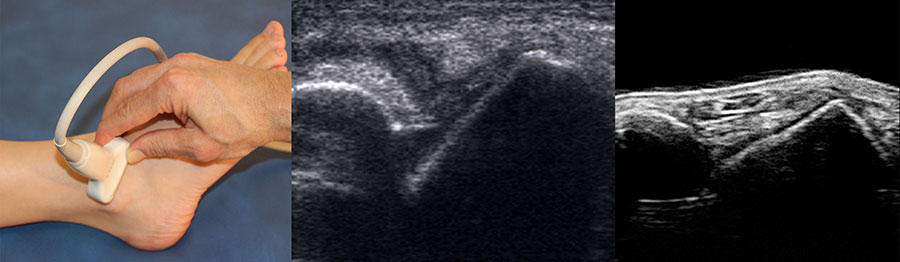

Mithilfe von Ultraschall (siehe auch „Sonographische Diagnostik an Sprunggelenk und Fuß“) lässt sich in der dynamischen Untersuchung eine Instabilität nachweisen 28. Ein Kalibersprung des Bandes sowie ein von Flüssigkeit umspülter Bandstumpf sind weitere sonographische Zeichen einer Bandruptur (Abb.3). Das Untersuchungsverfahren kann bei medialen Instabilitäten ebenso eingesetzt werden wie bei der lateralen Instabilität 29. Auch zum Ausschluss von Syndesmosenverletzungen hat die dynamische Ultraschalluntersuchung eine sehr hohe Sensitivität und Spezifität 30. Beurteilt wird in Höhe der Syndesmose die Translation der Fibula gegenüber der Tibia im Seitenvergleich.